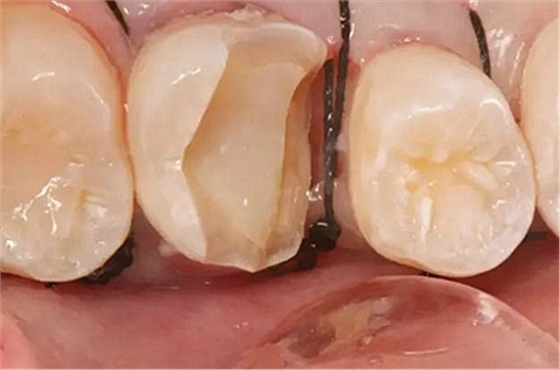

最后附幾例一次性根管治療+冠延長手術(shù)+高嵌體修復(fù)的病例,均為兩次完成。第一次就診:根管治療一次完成,后冠延長手術(shù),然后高嵌體預(yù)備,取模,第二次就診,拆線,試戴嵌體。具體在此不做詳細(xì)說明,圖中有詳解。

另外一個病例

病例3

該病例后期樹脂嵌體完成,為學(xué)生完成。沒有完成后的樹脂嵌體照片。病例已經(jīng)完成。